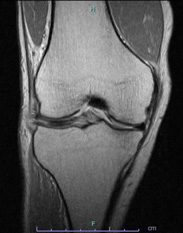

• 画像:損傷後外側半月板MRI画像(側面)

損傷後外側半月板MRI画像(側面)

• 画像:損傷後外側半月板MRI画像(正面)

損傷後外側半月板MRI画像(正面)